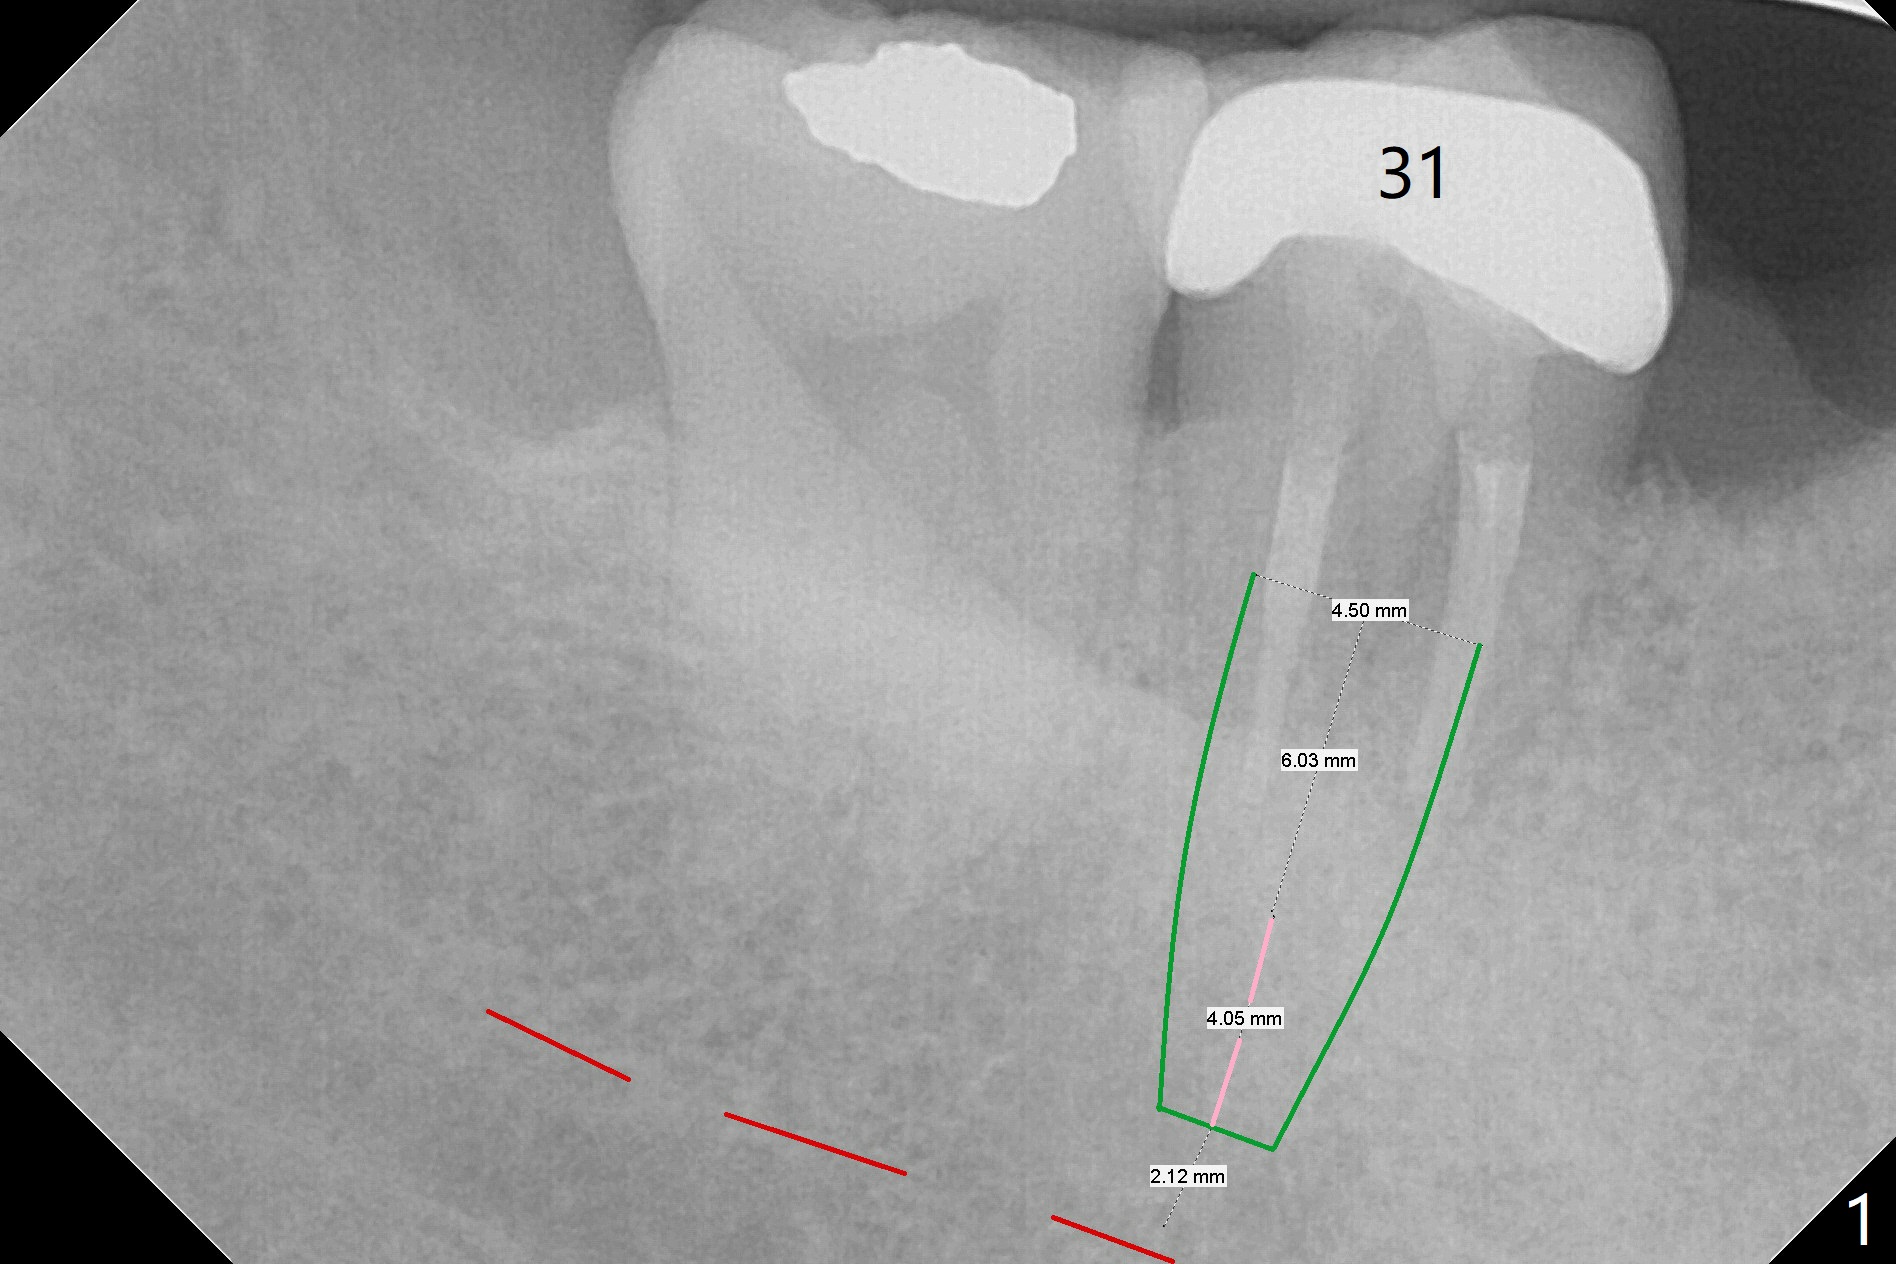

Mesiobuccal Abscess of 2nd Lower Molar

A 59-year-old woman has a mesiobuccal abscess at #31 (Fig.1, possible root fracture), while #30 is missing and replaced with a flipper.  After extraction, osteotomy will be initiated distolingual for 4 mm (pink line).  Do not lean too lingual apically.  If the lingual perforates, place bone graft before placing as small and shallow an implant as possible.  Check for perforation after each drill.  The patient will return for CBCT one day before surgery.  Also take photo for the abscess.